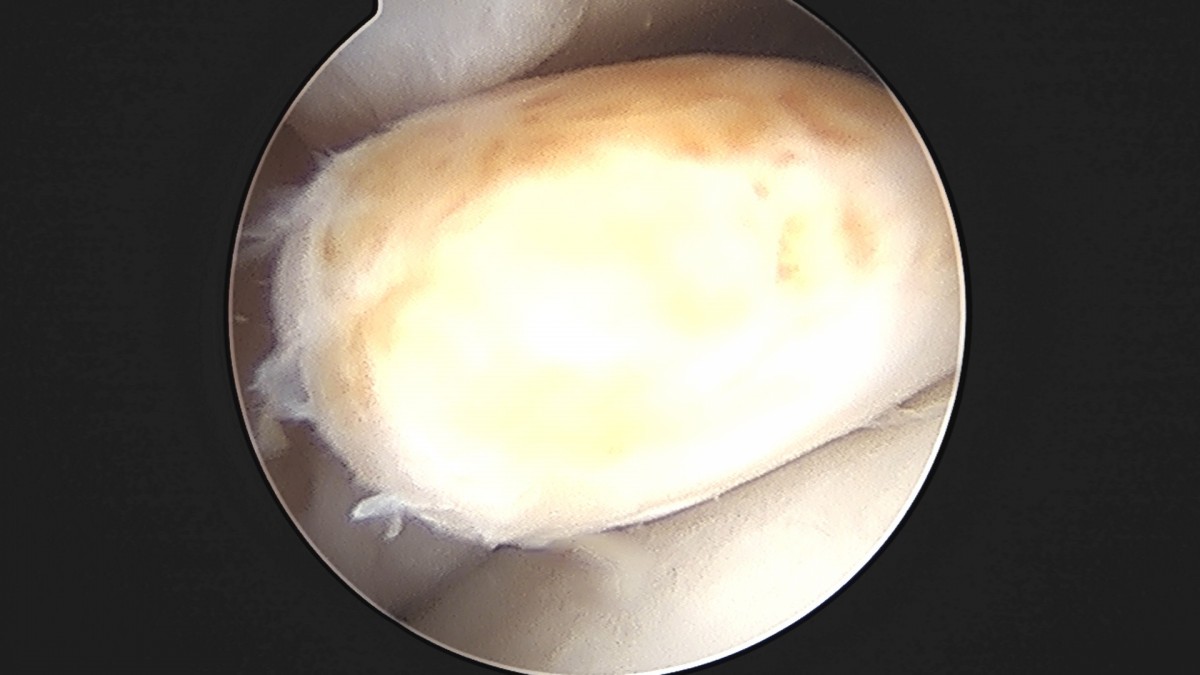

이재상원장님 발목 활액막 절제술 및 인대 봉합술 정보O 환자

작성자 최고관리자 댓글 0건 조회 797회 작성일 25-09-16 15:23